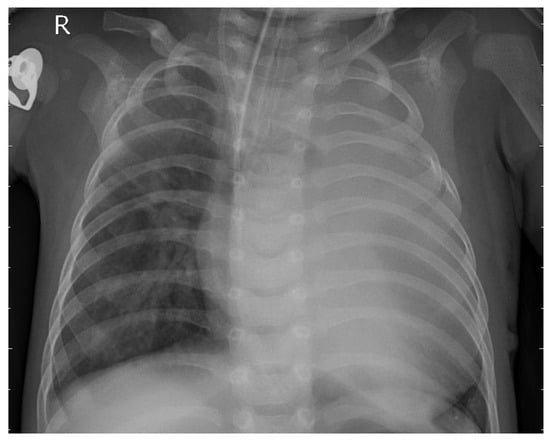

3.1. Dataset

3.2. Preprocessing